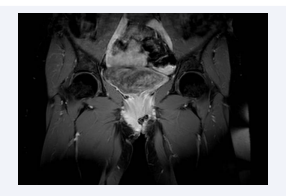

From July 11 to July 15, 2022, she received RT to the vulvar lesion (total dose of 20 Gy, fractionation of 400 cGy/day). The pelvic RMI of March 2023 showed progression disease so she received carboplatin AUC 2 on days 1, 8, of a 21-day cycle schedule until June 2023. An MRI performed on May 2023 revealed a stable 3 cm lesion in the left vulvar region, infiltrating the vaginal orifice and the distal third of the left lateral vaginal wall, as well as the left ischiocavernosus and bulbospongiosus muscles, reaching the medial cortical profile of the left ischiopubic ramus (Figure 3). Due to the onset of hearing loss, the patient was switched to follow-up care. A biopsy of the left vaginal neoplasm confirmed recurrent ACC.

Figure 3: Pelvic MRI with constrast showing 3 cm lesion in the left vulvar  region, infiltrating the vaginal orifice and the distal third of the left lateral  vaginal wall, as well as the left ischiocavernosus and bulbospongiosus muscles,  reaching the medial cortical profile of the left ischiopubic ramus.